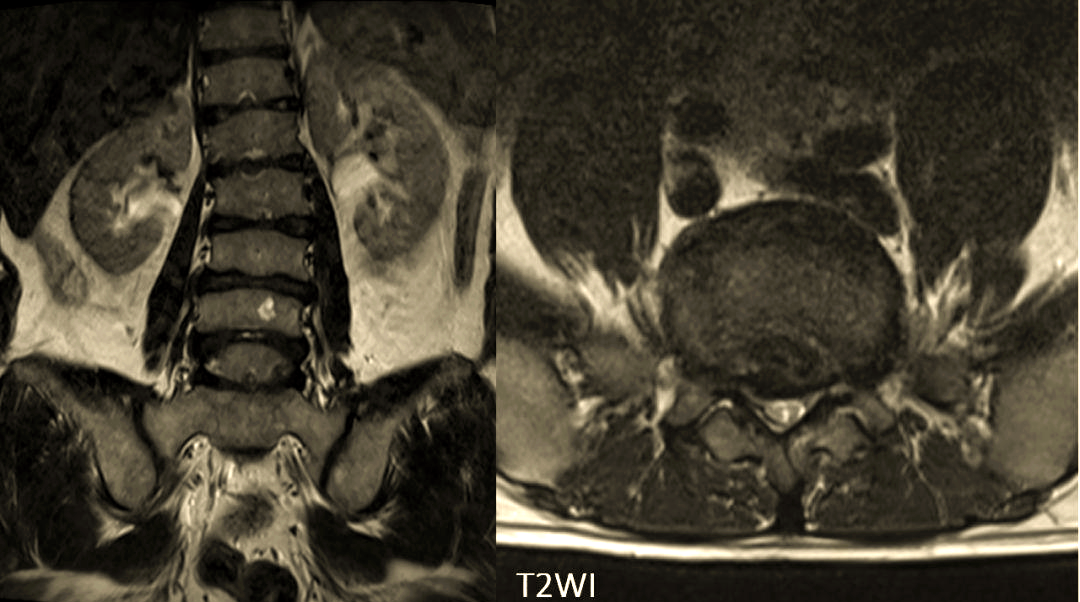

症状性胸腰段椎间盘突出为休门氏病的特殊表现

胸腰段椎体休门氏病所致脊柱后凸畸形一例

图片尺寸750x750